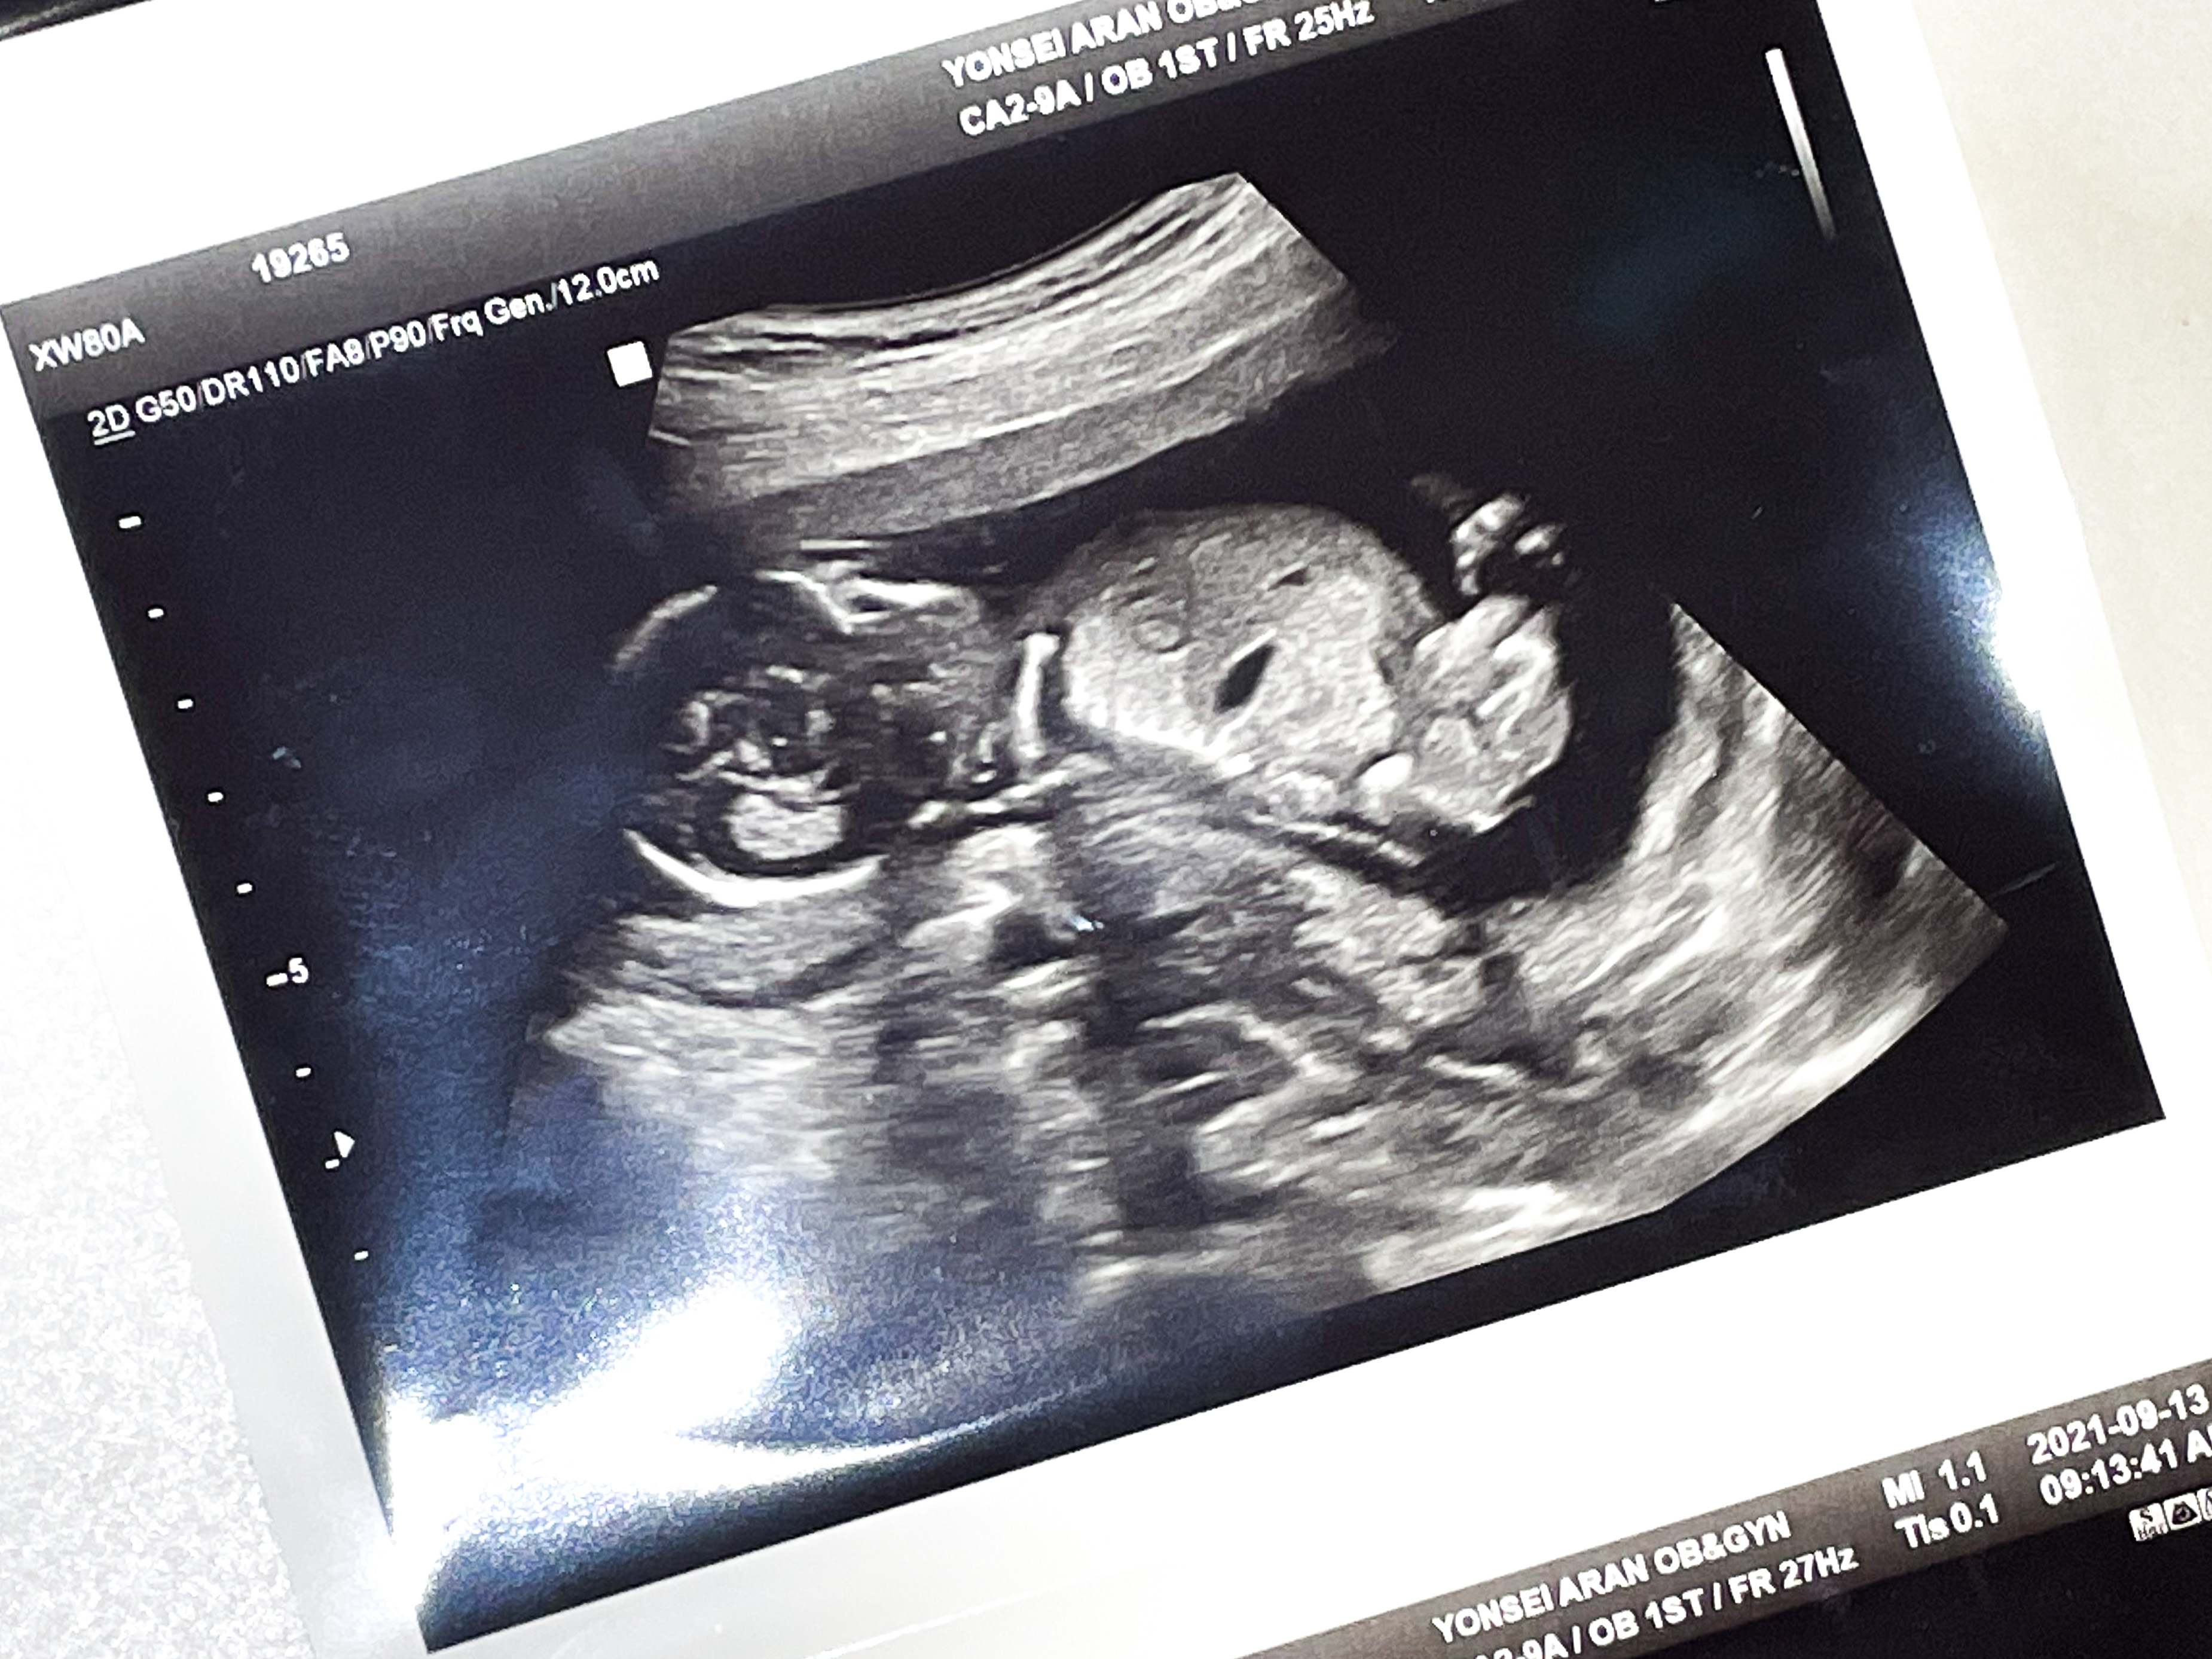

원장쌤께 혹시 아들인가요..?하고 여쭤보니

아직 안봐드렸었냐며,

바로 초음파로 정확하게 찍어서 프린트 해주셨다.

각도법으로 확인했던 그대로 아들이었다!

(단톡방 마다 저 위에 초음파 사진을 보냈는데 우리 엄마와 시어머니만 뭔지 알아보셨다..ㅋㅋ)